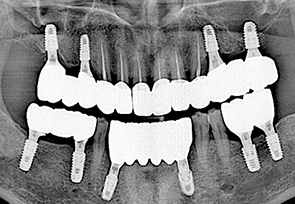

before

after